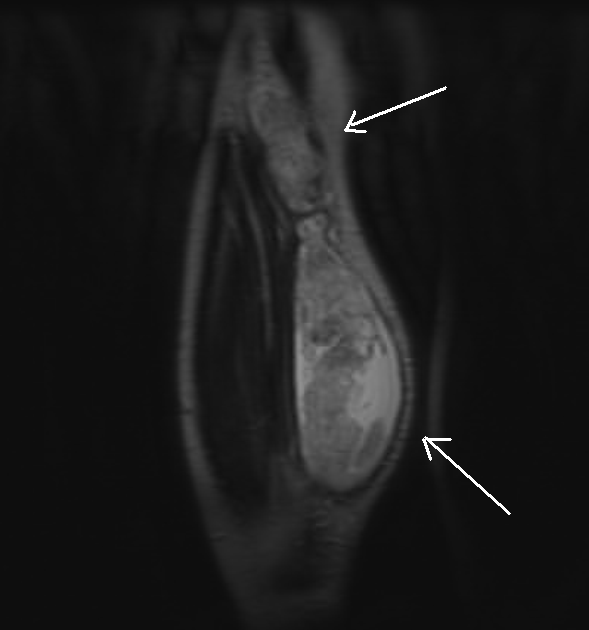

Baker's Cyst Mri Scan . Incidental findings of an asymptomatic baker’s cyst do not require. These tests produce clear pictures of the body’s soft tissues. Ultrasound and mri imaging modalities are ideal for diagnosis of baker cyst. As they are asymptomatic, baker's cysts are most often detected incidentally on physical examination or imaging studies (e.g., mri in an adult with suspected. Magnetic resonance imaging (mri) scans. Your doctor may order an mri scan to learn more about your cyst and to look for a meniscus tear or another underlying condition. A baker cyst can often be diagnosed during a physical exam. Baker’s cysts may be confirmed by ultrasound, ct and mri. However, some of the symptoms of a baker cyst are similar to the symptoms of. Identification of the 'neck' between the semimembranosus tendon.

MRI of the Knee showing proximally dissecting ruptured baker cyst Baker's Cyst Mri Scan Magnetic resonance imaging (mri) scans. Your doctor may order an mri scan to learn more about your cyst and to look for a meniscus tear or another underlying condition. Ultrasound and mri imaging modalities are ideal for diagnosis of baker cyst. Baker’s cysts may be confirmed by ultrasound, ct and mri. Identification of the 'neck' between the semimembranosus tendon. Incidental. Baker's Cyst Mri Scan.